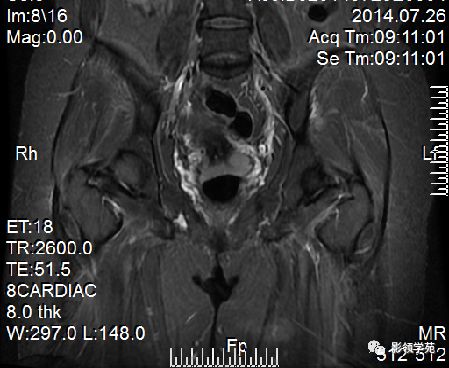

DWI显示淋巴结肿大